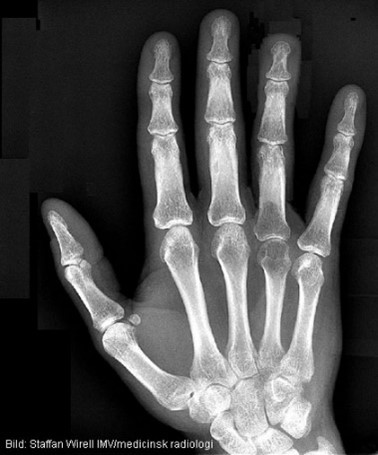

Ses något patologiskt?